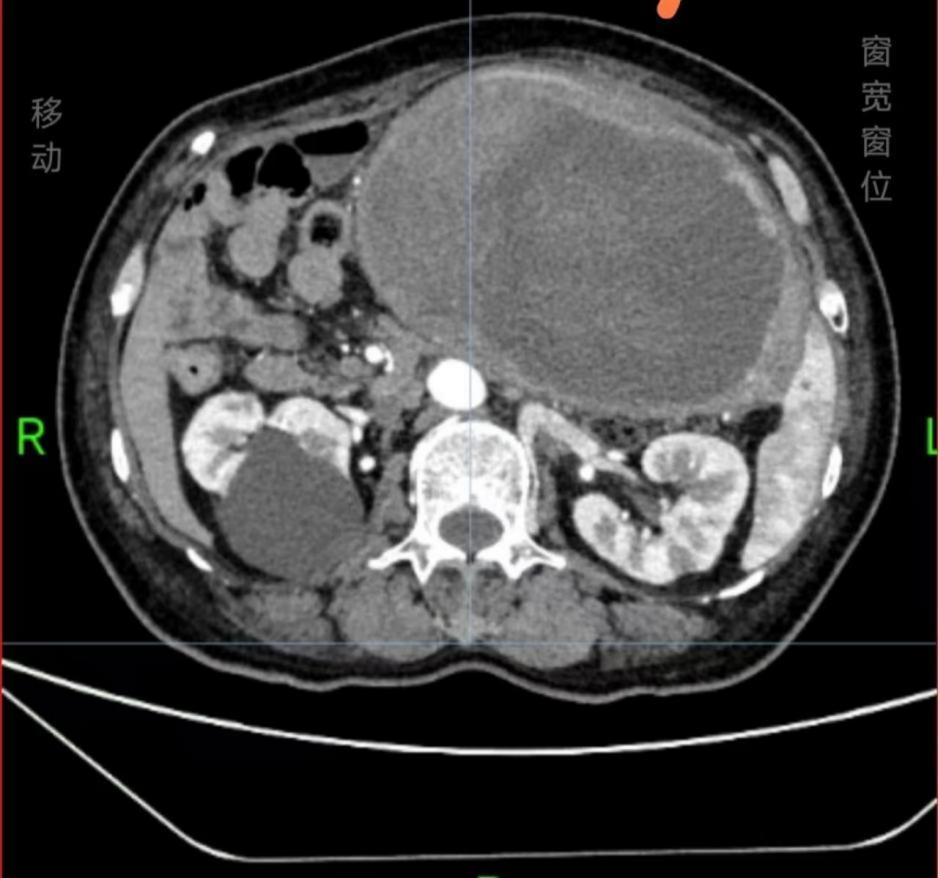

患者患血友病数十年,4年前发现腹腔肿物,辗转多家医院寻求手术治疗,均因手术风险高建议保守治疗,但保守效果并不理想,腹腔肿物不断增大。2月前患者出现腹痛加重和肠梗阻症状,腹腔肿物已达19.3*10.9cm,了解到医院高超的手术水平和丰富的血友病救治经验,遂来院求医,首诊于消化内科,后转入胃肠外科。

进行了充分的手术准备后,在胃肠外科张光永教授指导下朱健康团队为患者进行了手术治疗,术中发现假肿瘤为胃来源,和横结肠及部分小肠黏连紧密并致肠梗阻,团队克服肿瘤巨大、腹腔黏连严重且需多器官联合切除等重重困难,将肿瘤及部分结肠、小肠切除,术后病理证实为血友病假肿瘤。患者术后恢复顺利,现已康复出院。

血友病假肿瘤是血友病患者因凝血功能障碍导致的一种罕见并发症,本质是肌肉、骨骼及其他组织发生的囊性血肿。血友病患者因凝血因子缺乏,轻微创伤或自发性出血后,若凝血因子替代治疗不充分,血液在肌肉、骨骼及其他组织内持续积聚,形成包裹性血肿。长期反复出血使血肿增大,压迫周围组织,类似肿瘤表现。